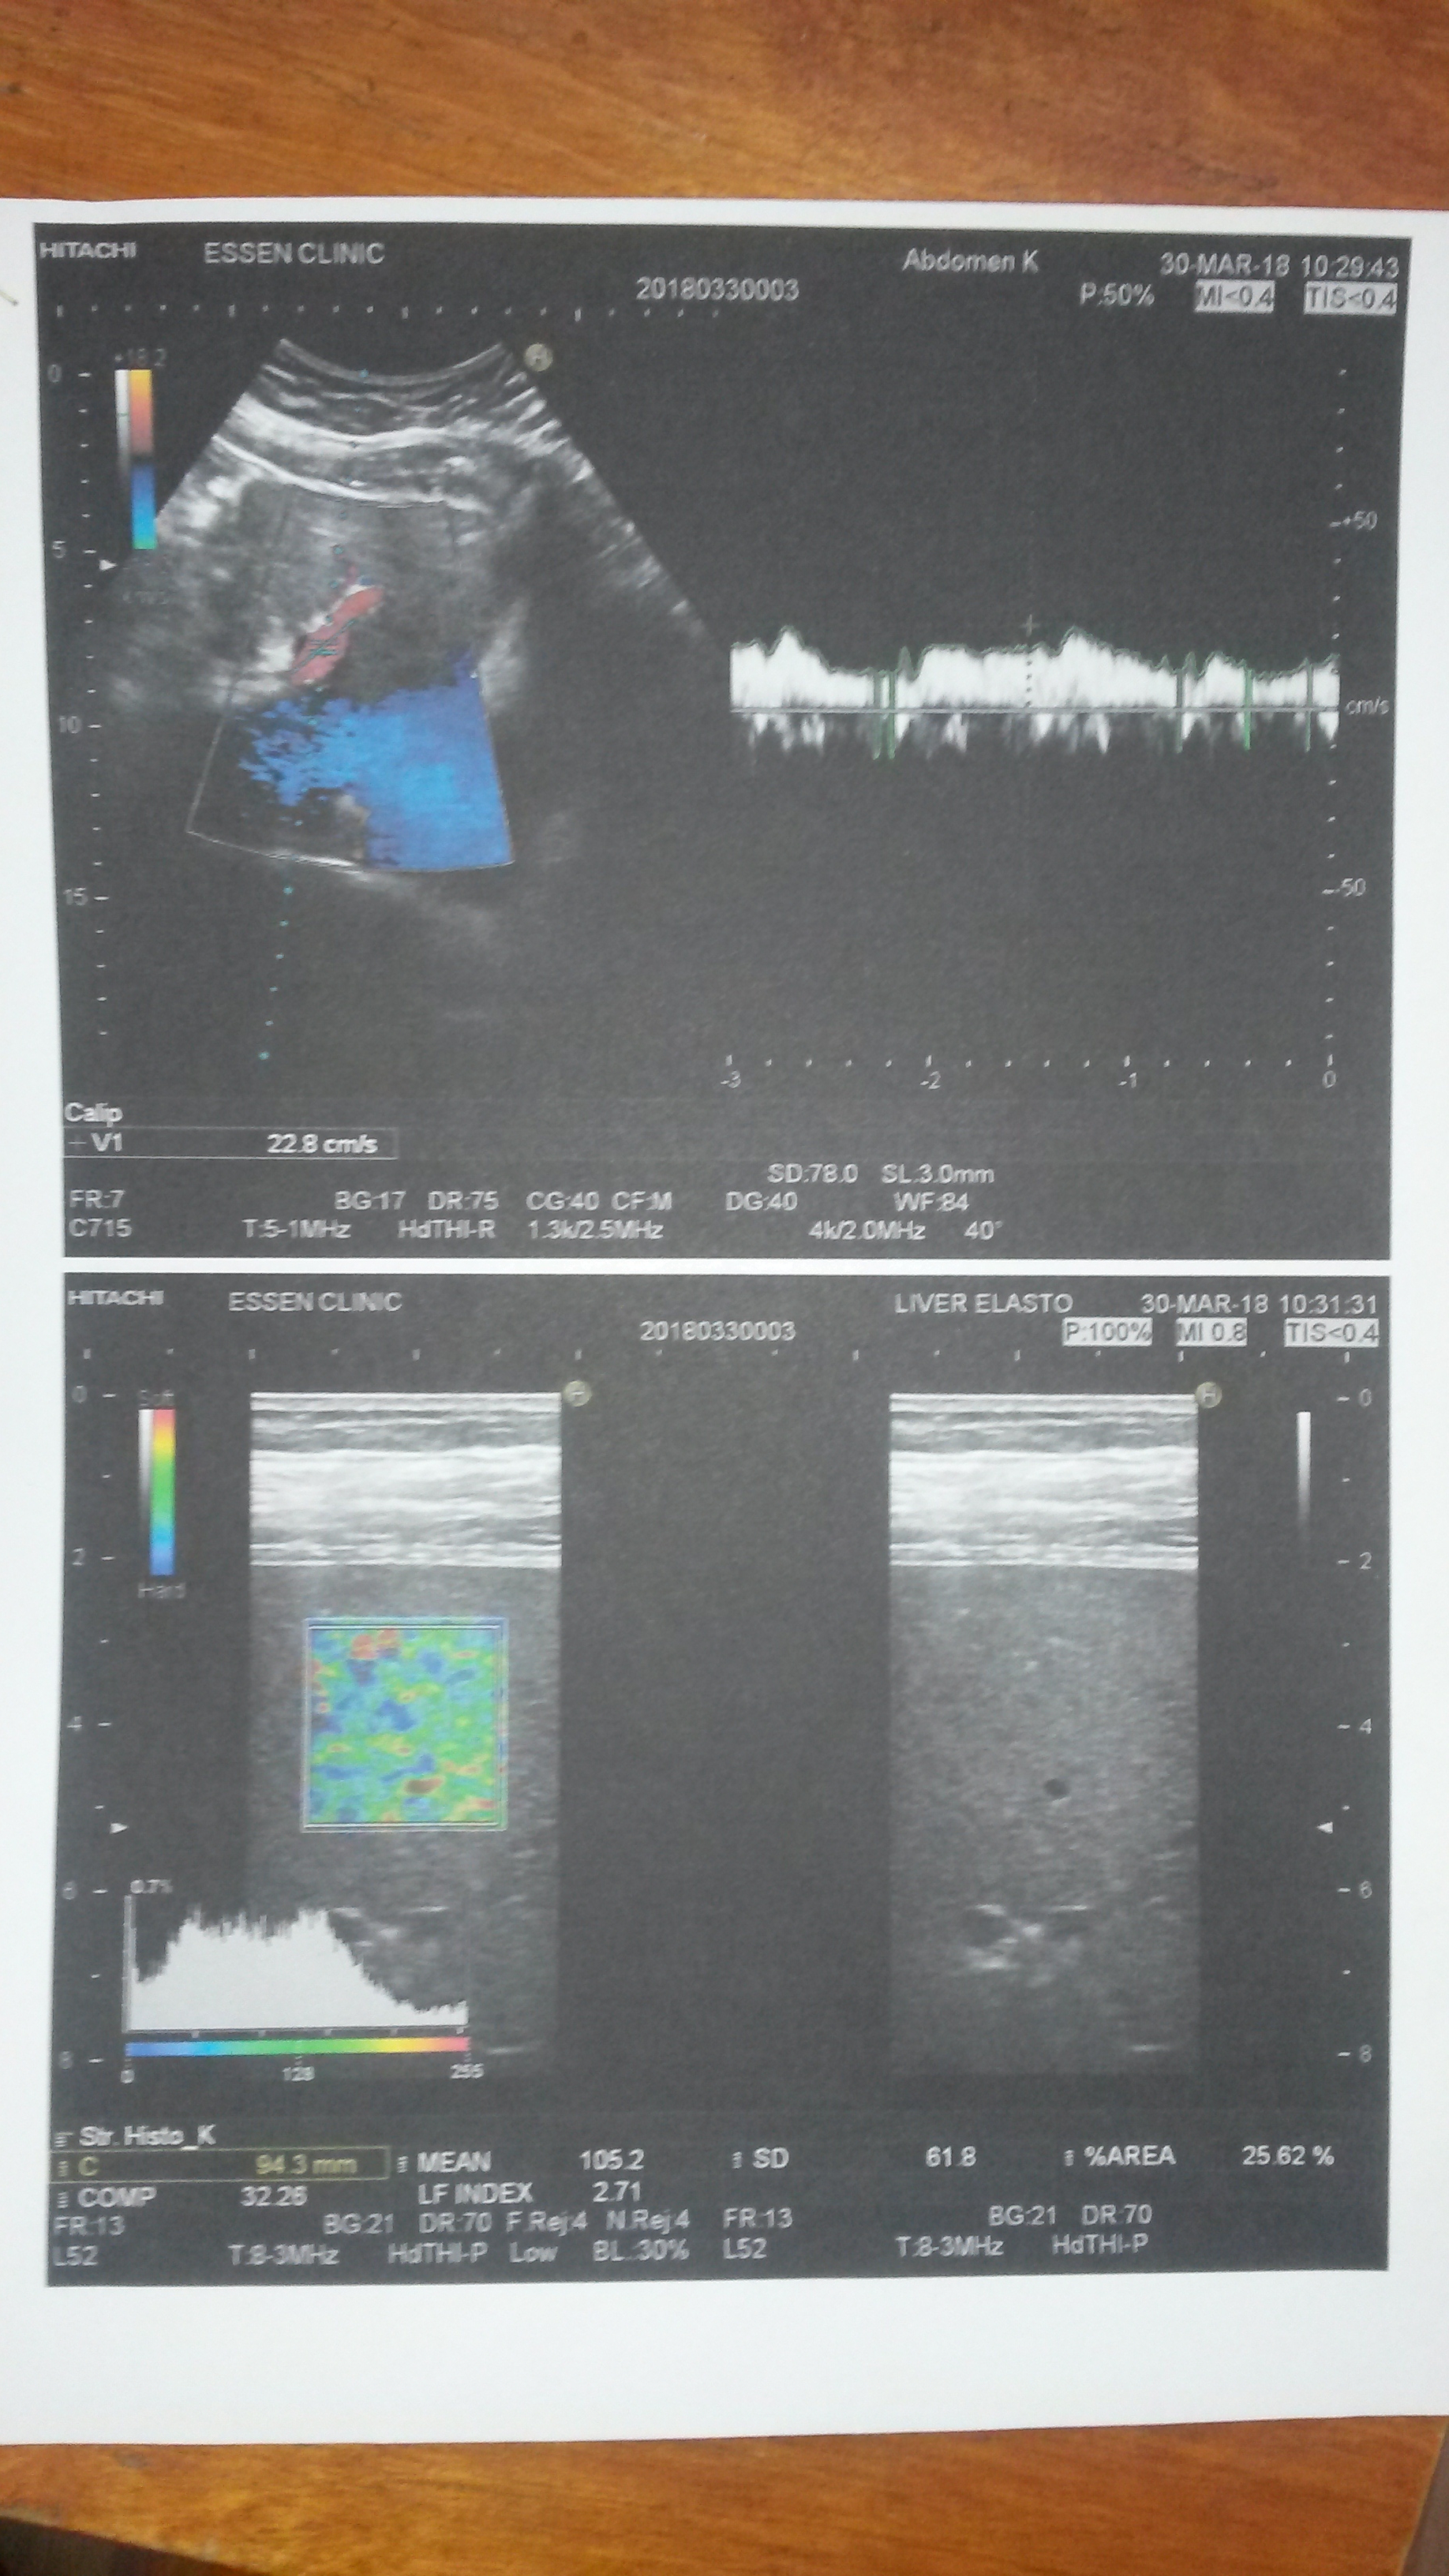

У меня чуть позже тоже был результат биопсии на руках, но в институт меня не послали (закончился эксперимент к тому времени). Я сам поехал. В Ессентуках Эссен-клиник. Заплатил 1600 со своего кармана. Сделал эластографию. Дождался когда мне результат выдадут на руки и только после этого достал результат биопсии. Вместе с врачом внимательно сравнили (он виду не подал, но ему было интересно) результат вышел практически 1:1.

Биопсия: F1-F2 ИГА по Кнодель 4 балла (0+1+3). А1 по Метавир.

Эластография: Фиброз F1-F2.

Эластографист тогда еще сказал, что абсолютно уверен в своих измерениях. Стал мне на мониторе что-то показывать. Говорит тут все четко, без сомнений.